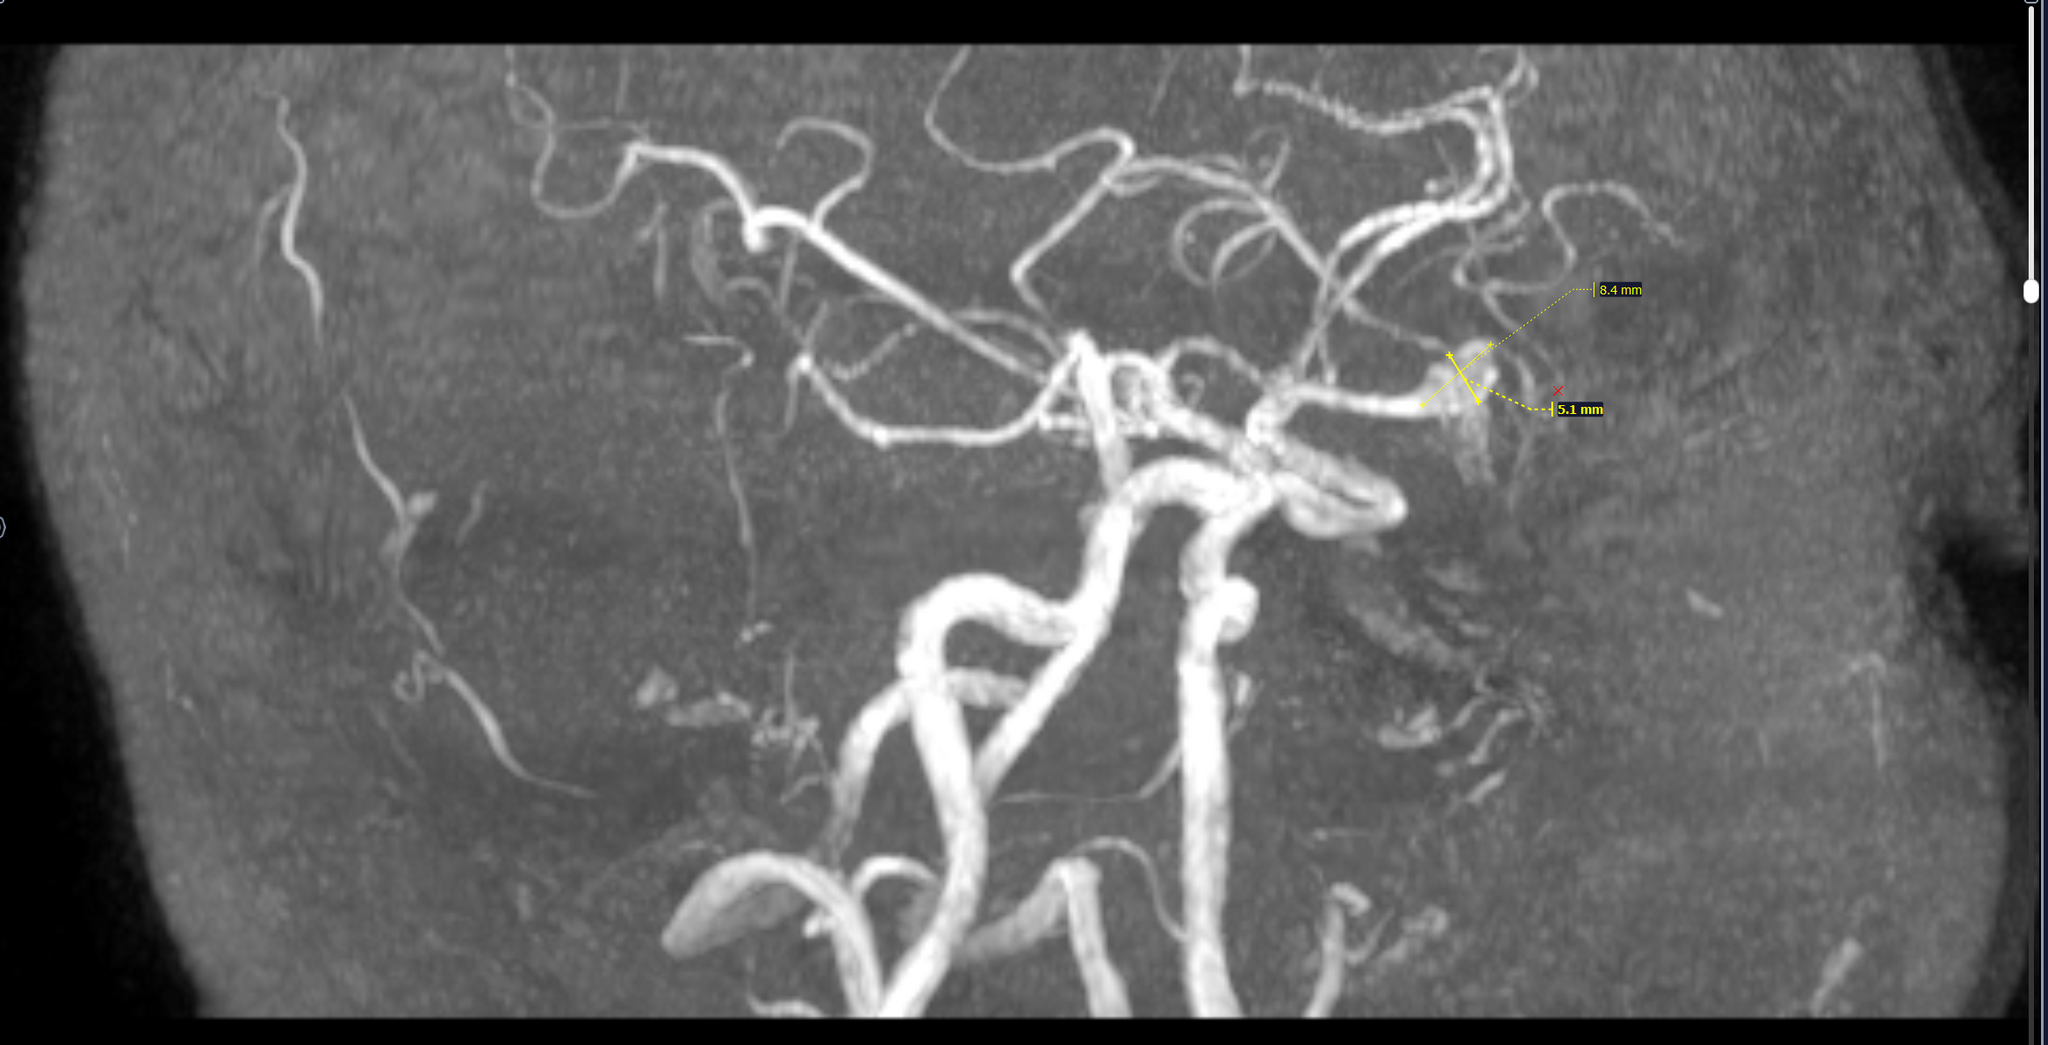

МР-картина мешотчатой аневризмы левой средней мозговой артерии на границе М1\М2 сегментов в области бифуркации размерами до 8.4х5.1 мм.